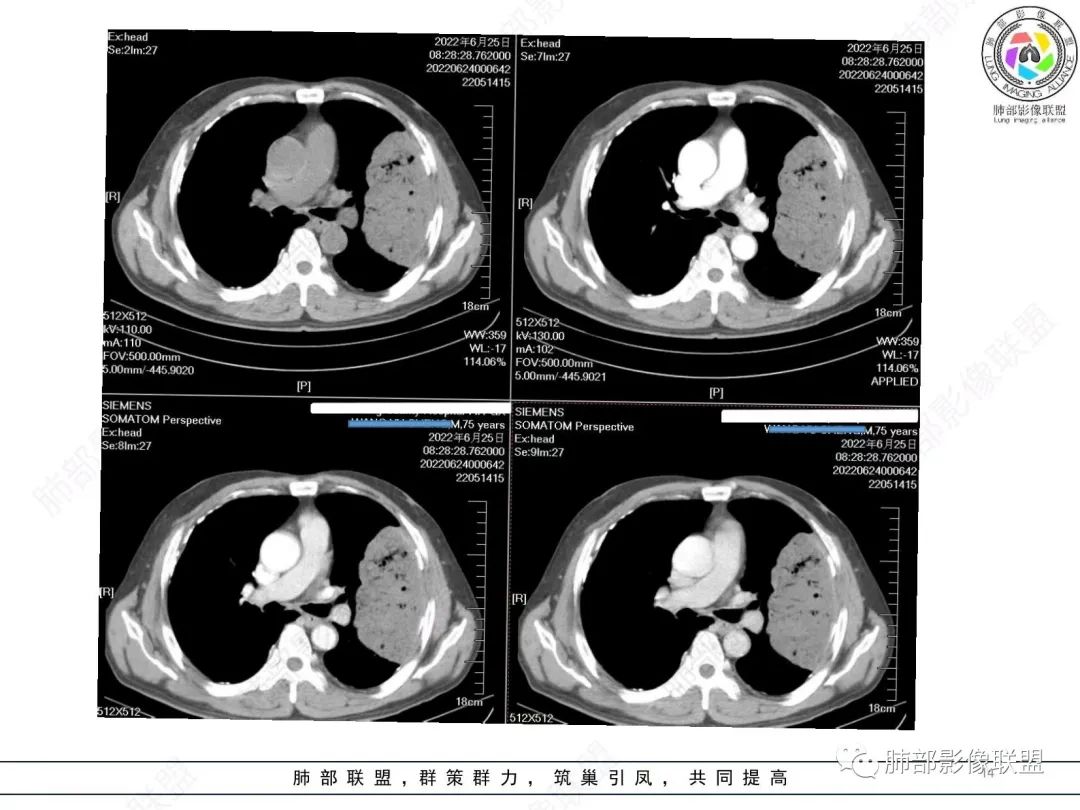

左肺上叶大肿块,膨胀性生长,边界清,密度较低,见部分坏死区,强化弱,肿块见支气管充气V扩张征,分布僵直,枯树枝特点,另一个重要特点血管造影征,淋巴瘤,肿块长轴与胸膜平行,与隐球菌鉴别,隐球荚膜抗原检查,明确诊断经皮肺穿刺。另胸膜钙化(问诊既往有无患胸膜炎病史)。

老年男性,糖尿病病史,消瘦、乏力三个月,影像表现左肺上叶胸膜下团块,有一定张力,内部疏松,可见支气管影及坏死区,增强病灶边缘环形强化,内部未见强化,考虑炎性肉芽肿病变,隐球?奴卡?放线菌?鉴别淋巴瘤。

左肺上叶胸膜下肿块,宽基底与胸膜相连,跨叶裂,边缘清晰膨隆,其内支气管充气,部分扩张、僵直,无明显强化,血管造影征,考虑淋巴瘤,鉴别腺癌

左肺胸膜下巨大占位,跨叶裂,宽基底与胸膜相连,胸膜钙化,平扫密度较低,强化不明显,可见内部血管显影,支气管充气征和扩张,考虑为恶性,倾向于淋巴瘤

左侧胸腔巨大肿块,跨叶生长,临近胸膜钙化,边缘模糊,可见支气管影,定位肺内,增强后轻度强化,边缘见血管影,考虑淋巴瘤,鉴别肉瘤

左肺上叶胸膜下肿块,膨胀性生长,边界清晰,密度不均部分坏死,未见强化,病灶内支气管迂曲扩张,病灶长轴与胸膜平行,胸膜下脂肪间隙存在,胸膜钙化,考虑放线菌?毛霉?鉴别淋巴瘤

支持淋巴瘤,左上肺大肿块,有分叶,边缘光整,病灶内密度不均,可见支气管扩张征,增强后可见血管影征。周围肺野清晰。

左肺上叶肿块,宽基底与胸膜相连,跨叶裂,边缘清晰膨隆,可见小分叶,其内支气管充气,部分扩张、僵直,呈枯枝征,支气管达边征,增强无明显强化,可见血管造影征,考虑恶性病变,淋巴瘤,鉴别粘液腺癌。